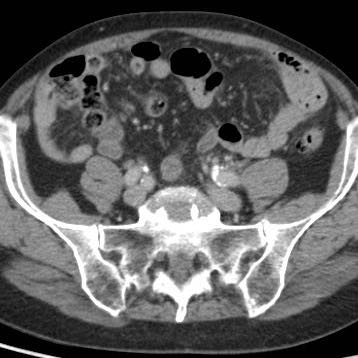

Ở người phụ nữ 56 tuổi này với CRP 180, siêu âm phát hiện dịch trong phúc mạc đục (*) và có thể thấy ruột thừa viêm với sỏi phân (mũi tên).

CT xác nhận hai sỏi phân ở hố chậu phải với hình ảnh khí bất thường, nghi ngờ viêm ruột thừa thủng.

Chọc hút dưới hướng dẫn siêu âm xác nhận dịch mủ.

Phẫu thuật cấp cứu phát hiện viêm ruột thừa thủng với nhiễm bẩn mủ bốn góc phần tư ổ bụng.